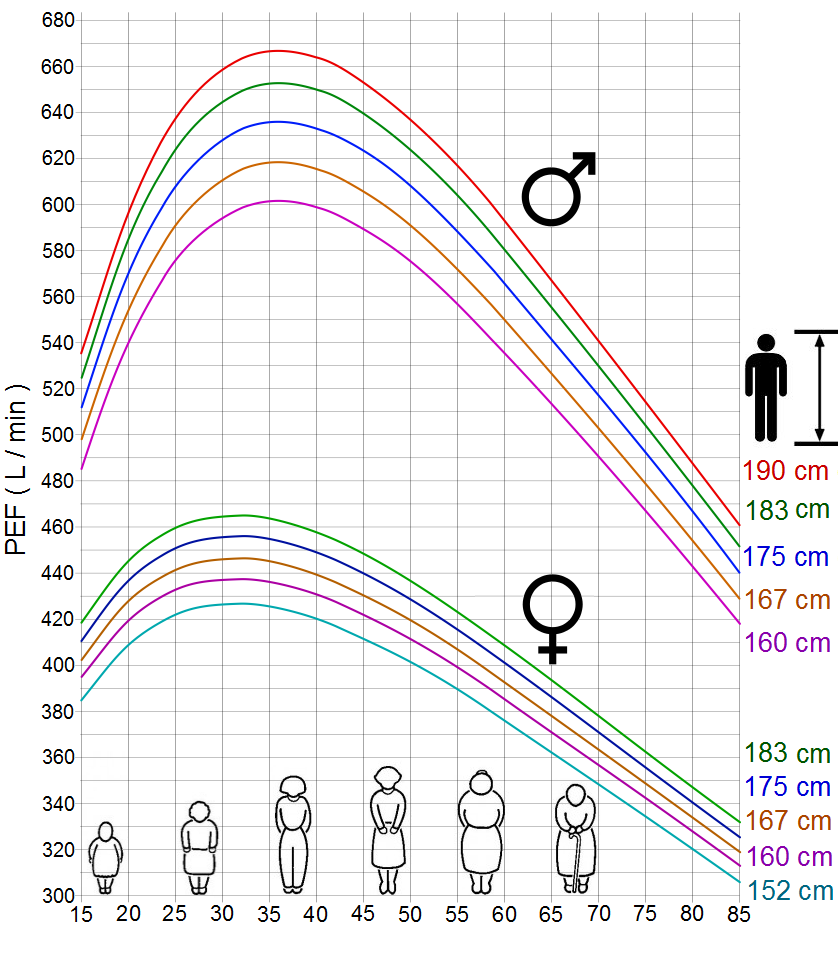

- Peak Expiratory Flow – this test can be done to measure the severity of airway obstruction.